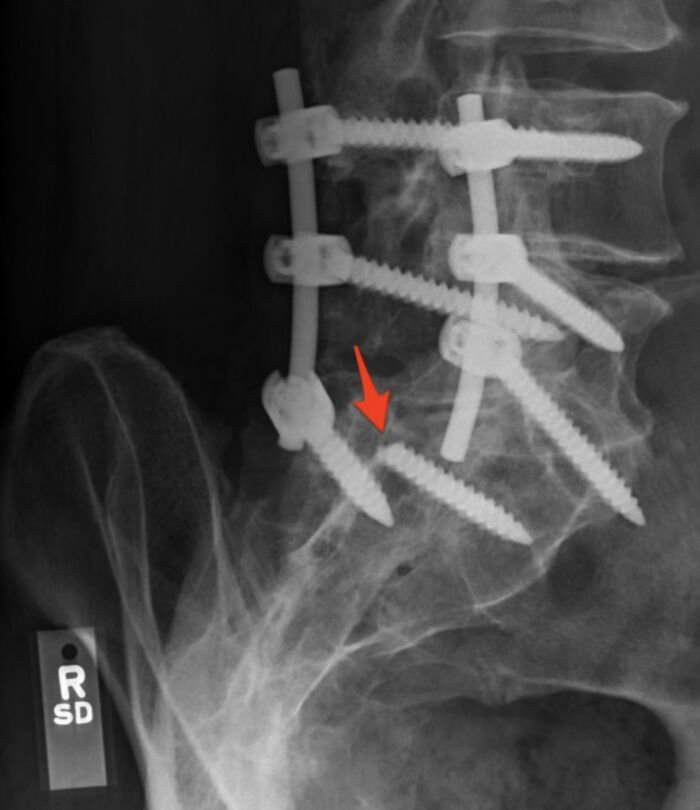

One Of The Screws Holding My Spine In Place Snapped

I had a L4-L5 / L5-S1 spinal fusion. I was sitting at my desk when I felt (and heard) a huge snap in my back. Almost immediately I couldn’t feel or move my left leg.

Turns out that one of the screws snapped. My surgeon was able to add another s***w but had to leave the broken piece in there. 0 out 10 stars - would not recommend.